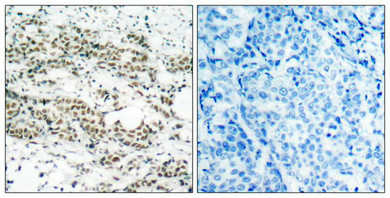

Immunohistochemical analysis of paraffin-embedded human breast carcinoma tissue using AFX(Phospho-Ser197) Antibody(left) or the same antibody preincubated with blocking peptide(right).